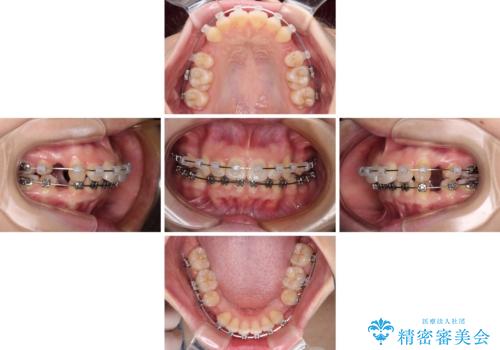

- メタルブラケット

- 1年1ヶ月

舌の突出癖があり、前歯の移動量も多くなるため、治療期間は長くなると予想されましたが、13ヶ月という予定の半分程度の期間で終えることができました。

※写真にある上顎装置はメタルブラケットではありません。メーカー在庫都合などにより別の装置を使用しております。